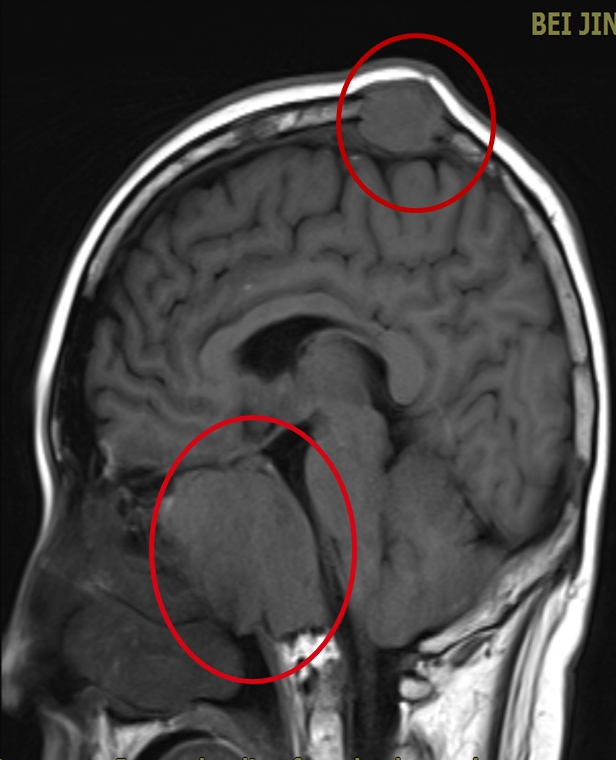

入北京博仁医院生命体征平稳,体格检查头部可见多个肿大包块,无压痛,伴视力下降、视物重影,心肺查体无异常。血常规无异常。肝肾功:总胆红素轻度升高。复查头颅核磁,颅骨可见多发骨质破坏,鞍区病灶为最大,约 47×47×43(mm),左颞部病灶压迫左颞叶脑组织向内移位。胸部 CT 可见肋骨、锁骨、肩胛骨多发的骨质破坏。

a. 颞部髓外包块压迫脑组织  b. 鞍区占位  c. 矢状位